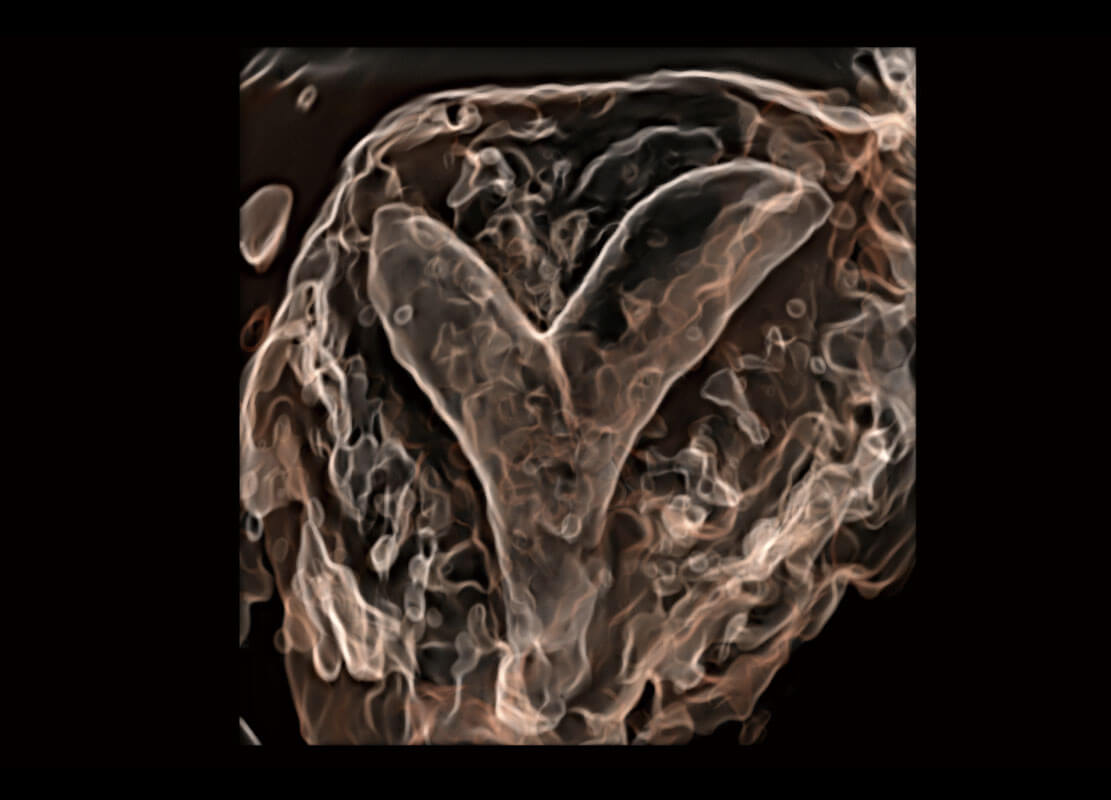

P60搭载一系列胎儿心脏成像技术,实现精细的胎儿心脏评估。

右室双出口